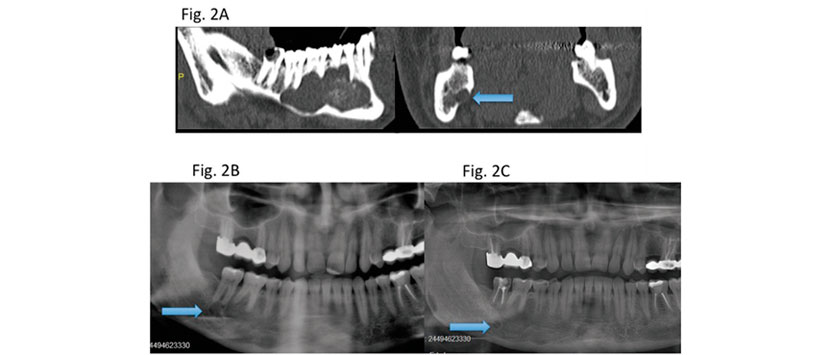

Debido a las altas tasas de recurrencia, que van desde 0% al 62% (6-8), hay diferentes opciones de tratamiento para OKCs. Estas modalidades de tratamiento han sido ampliamente dividido en dos categorías principales: enfoques conservadores, incluida la enucleación simple con o sin curetaje, descompresión o marsupialización, y enfoques agresivos, incluida la enucleación con osteotomía periférica, enucleación con la solución de Carnoy, crioterapia y resección (en bloque o marginal). Aunque los OKC son lesiones invasivas y agresivas, los investigadores aún buscan la mejor opción de tratamiento que daría lugar a una morbilidad mínima debido a la naturaleza benigna de la enfermedad La resección tiene la menor tasa de recurrencia entre las diversas opciones de tratamiento para OKCs; sin embargo, en comparación con otras modalidades de tratamiento, se asocia con morbilidades como el facial asimetría y la pérdida de la continuidad de la mandíbula. Por lo tanto, la resección se sugiere para lesiones grandes y recurrentes en ubicaciones anatómicas difíciles. (Figura 1)